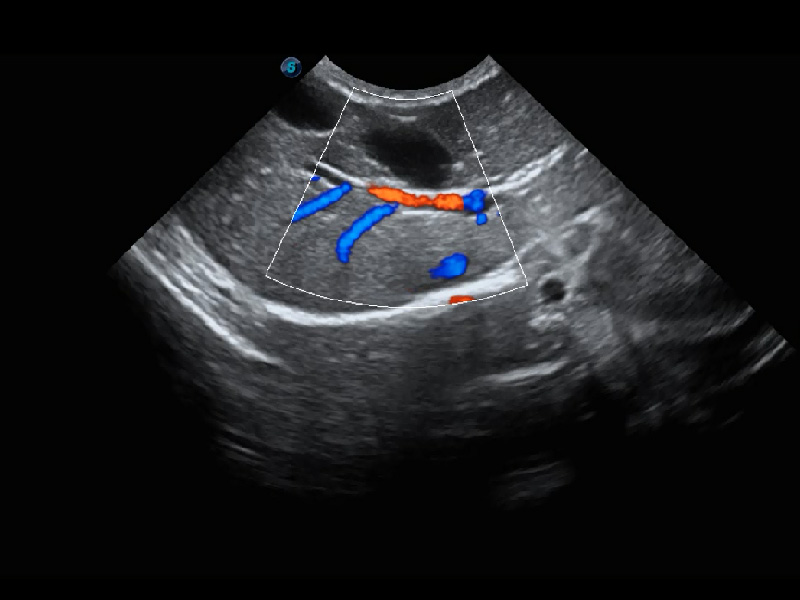

(犬)胆囊泥沙